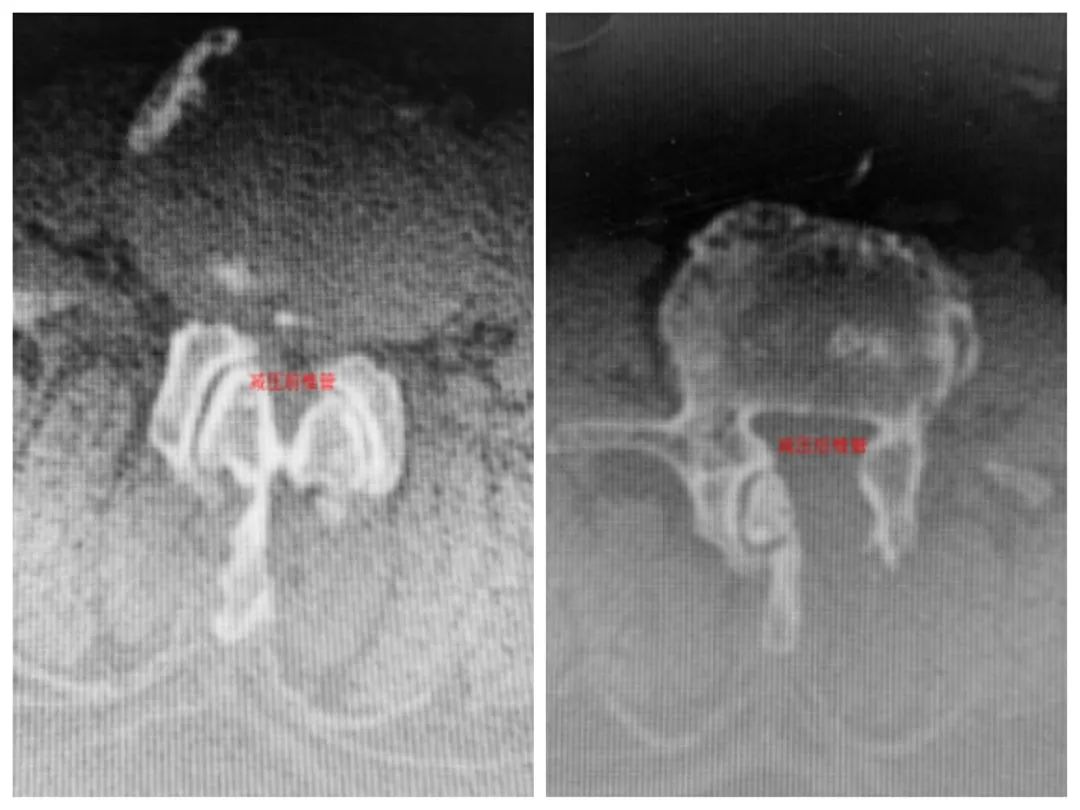

ULBD技术是应用脊柱内镜通过单侧椎板间入路进行双侧椎管和侧隐窝的减压,其手术切口仅1.5cm,出血量约20ml。和开放手术相比,既能够明显减小手术创伤,又能够达到和开放手术相同的减压效果。

2020年4月14日,在完善术前准备后,陈昌红博士脊柱外科团队为沈老先生进行了脊柱内镜下的单侧入路双侧腰椎管减压(ULBD)手术治疗。术后第2天下床行走的沈老先生发现折磨他半年多的腿不疼了,开心的老先生一口气绕病区走廊连续走了两圈。